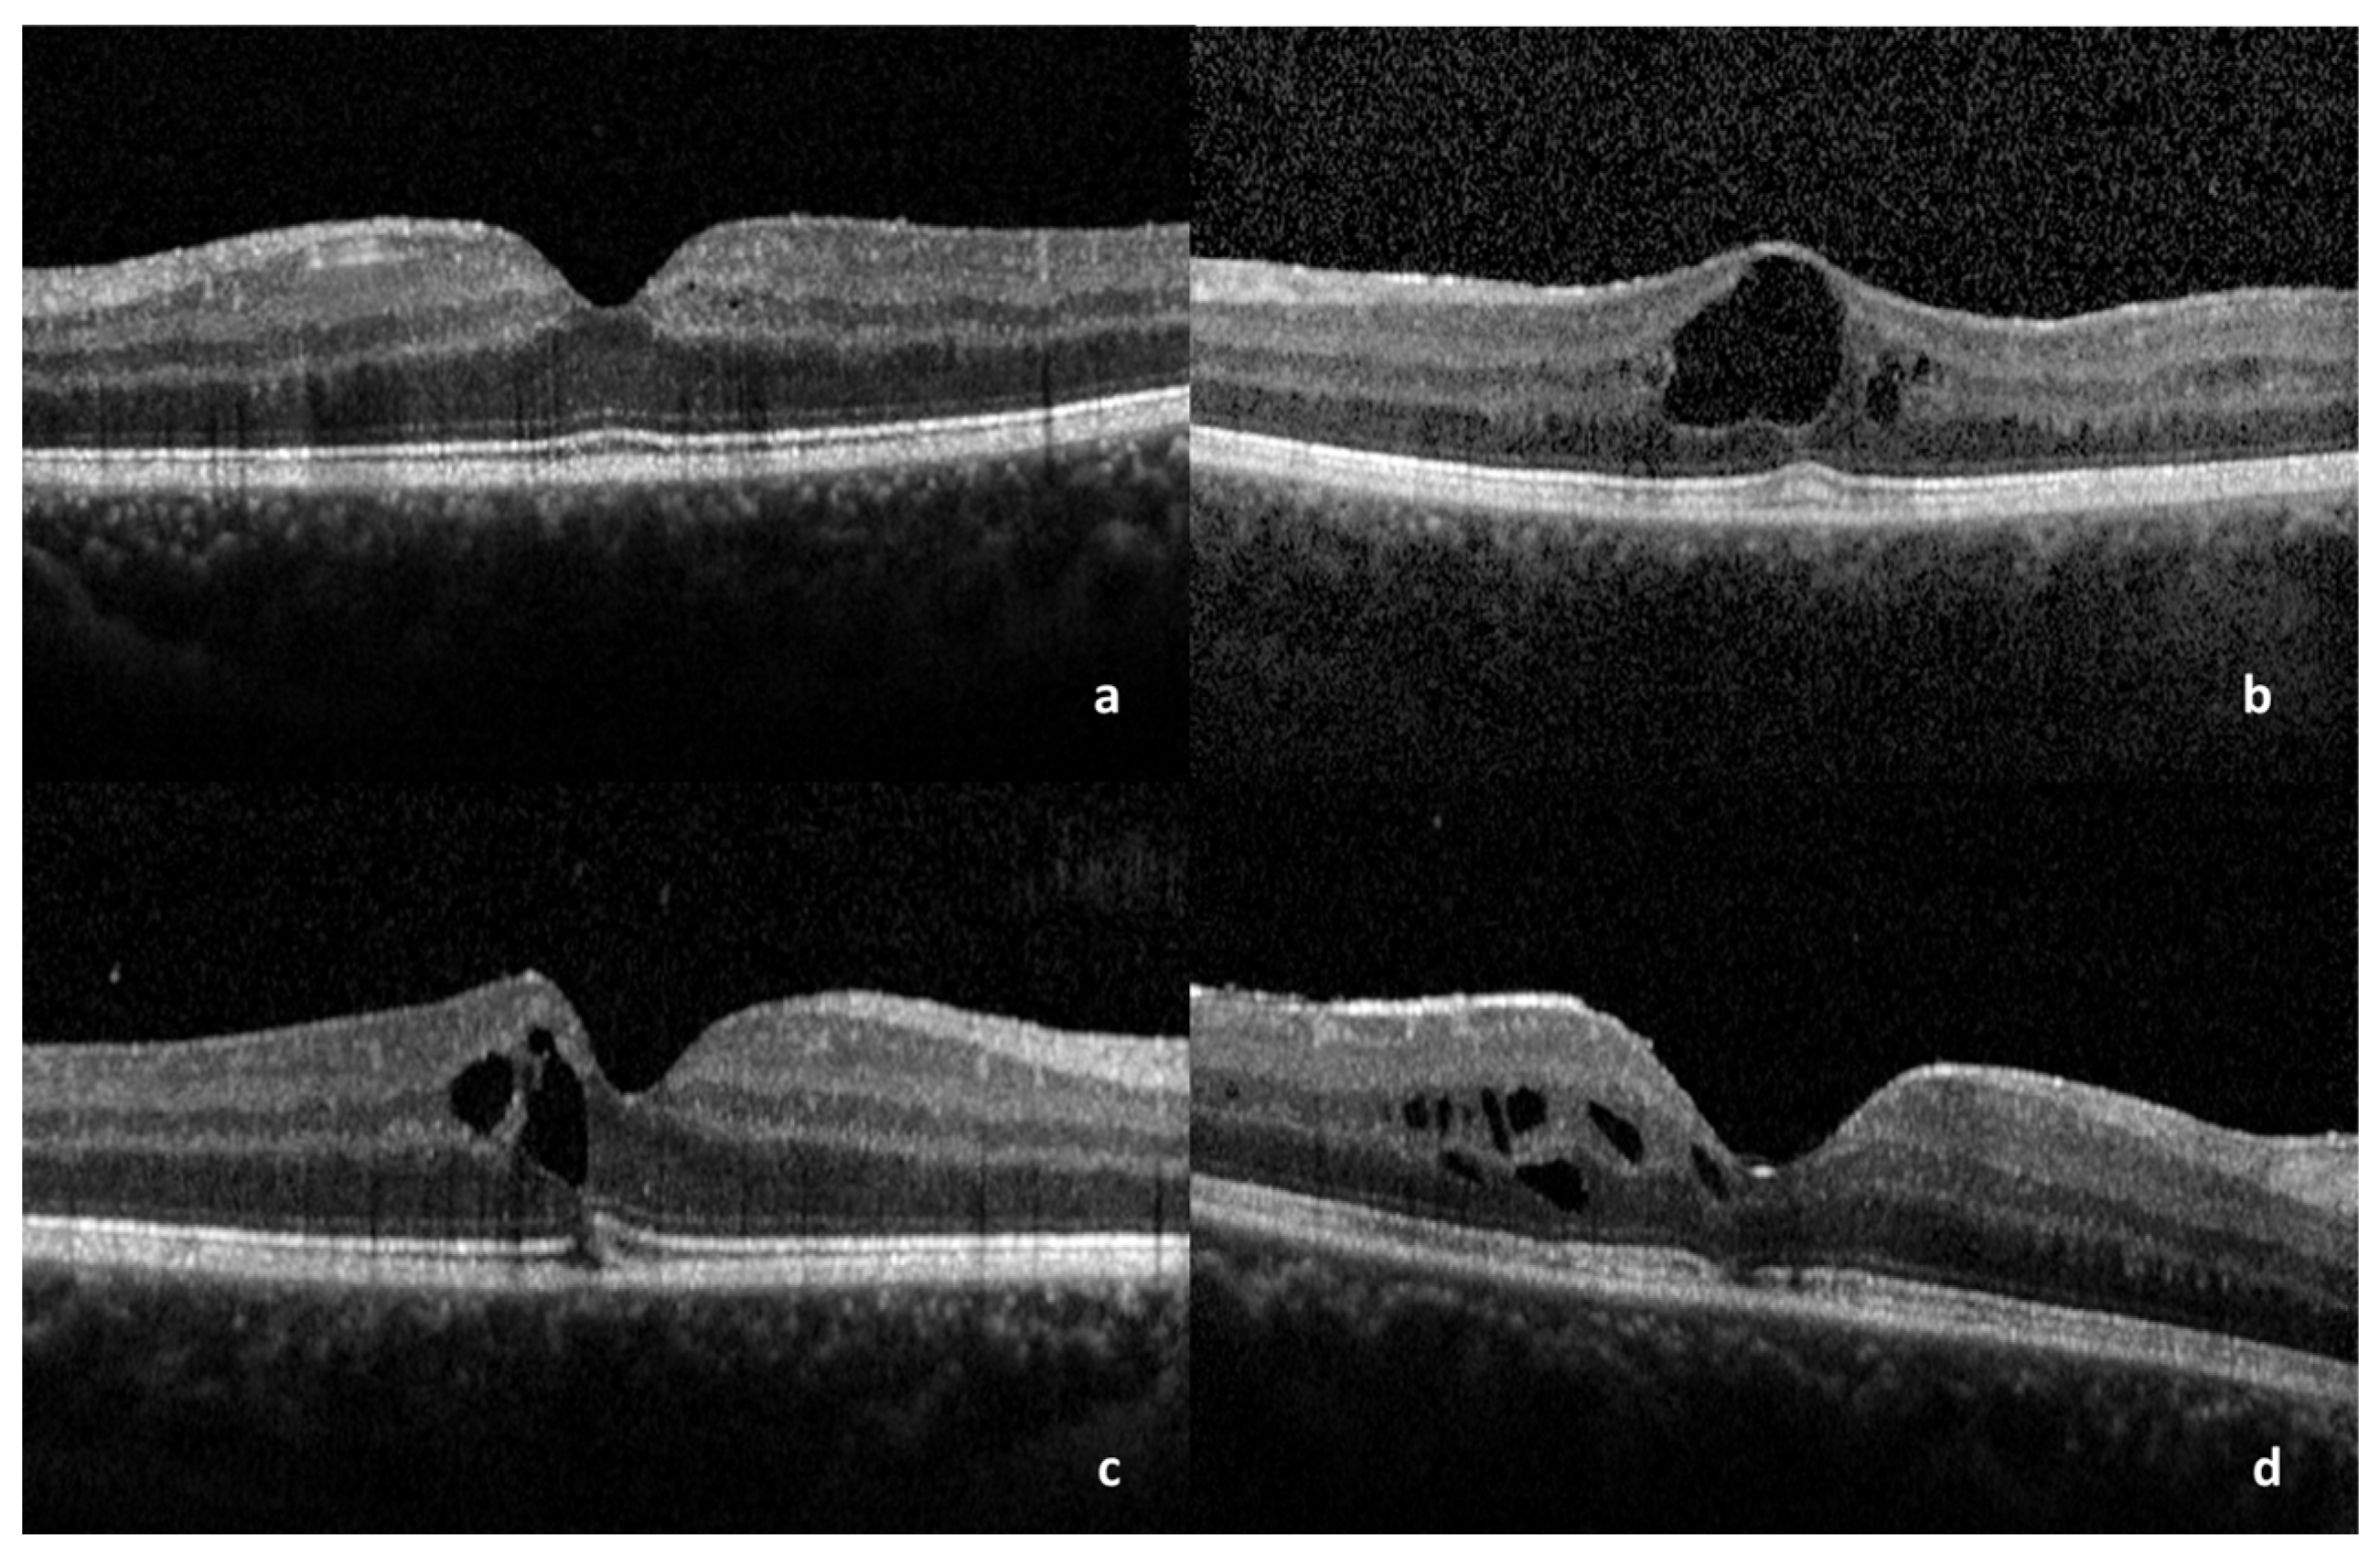

| Covariate | β Coefficients | Cumulative OR (95% CI) | p Value (Chi2 Test) |

|---|---|---|---|

| EZ disruption | −5.6 (−9.5–−2.5) | 0.004 (7.83 × 10−5–0.08) | 0.00021 |

| CME | −4.4 (−7.4–−1.9) | 0.012 (0.001–0.142) | 0.00021 |

| CST | −2.2 (−3.6–−0.19) | 0.106 (0.028–0.304) | 3.16 × 10−6 |

| SRD | −1.9 (−3.9–−0.12) | 0.146 (0.021–0.887) | 0.037 |